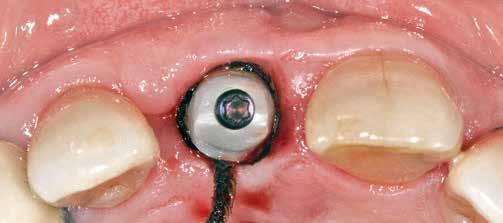

Az eljárást helyi érzéstelenítés mellett végeztük (4%-os articaine-hidroklorid 1:100 000 adrenalinnal). Papillakímélő, U alakú palatális bemetszést végeztünk, teljes vastagságú nyálkahártyalebeny preparálás történt, a lebenyt bukkálisan feltekertük (5. ábra). A lebeny bukkálisan feltekert részén de-epitelizációt végeztük el, amellyel kompenzálni tudtuk a bukkális lágyszöveti defektust. Szakaszos előfúrást végeztünk, és a bredent copaSKY 4x10 implantátumot 30 Ncm behajtási nyomatékkal helyeztük be (6. ábra). Az implantátumot 1 mm-re szubkresztálisan helyeztük be, hogy később szélesebb emergenciaprofilt tudjunk kialakítani (7. ábra). Az egyedi ínyformázó úgy készült, hogy kompozitot vittünk fel a titánbázisra, és így formáztuk a lágyszöveteket a transzgingivális gyógyulási fázis során (8. ábra). Az egyéni ínyformázó tulipán formájú, hogy kialakítsa a kívánt emergenciaprofilt. A lágyszövetet feszülésmentesen zártuk #6/0 nem felszívódó, monofil fonallal (Optilene, B. Braun Deutschland; 9. a–b. ábra). Posztoperatív röntgenfelvétel készült, ami alapján az implantátum a szomszédos fogakkal párhuzamos elhelyezést mutatott (10. ábra). Posztoperatív utasításokat adtunk a páciensnek a műtéti terület körüli szájhigiénia fenntartása érdekében. A beavatkozást követő egy héttel a varratokat eltávolítottuk, és a kezelt terület kielégítő gyógyulást mutatott (11. ábra). A 4 hónap utáni késleltetett terhelést a páciens kívánsága szerint terveztük.

uni.fit titánalapra (bredent medical). Az implantátum körül a bukkális lágyszövet megfelelő vastagságot és kedvező ínykontúrt mutatott (12. a–b. ábra). Az egyedi ínyformázó eltávolítása után egészséges implantátum körüli lágyrészgallér

volt megfigyelhető (13–14. ábra), ezen kívül közvetlenül a műtét előtt intraorális vizsgálatot végeztünk a lágyszöveti profil megállapítása érdekében. Ezt követte a scanbody behelyezése, így digitális lenyomat készült az implantátum pozíciójáról (15. ábra). Ugyanezzel a technikával rögzítettük az antagonista fogívet és a harapást is. Az így kapott STL-fájlokat digitálisan továbbítottuk a fogtechnikai laboratóriumba. A titánalapra PMMA ideiglenes koronát készítettünk a proximális és marginális illeszkedés ellenőrzése érdekében, valamint a megfelelő harapás elérése céljából (16–17. ábra) Miután az összes igazítás elkészült, ismételt vizsgálatot végeztünk. A végleges hibrid csavarrögzítésű, teljes kontúrú cirkóniumkoronát titánalapon erősen polírozott szubgingivális résszel készítettük el, és 25 Ncm nyomatékra húztuk (18. ábra). Kiváló árnyalategyezést és klinikai eredményt